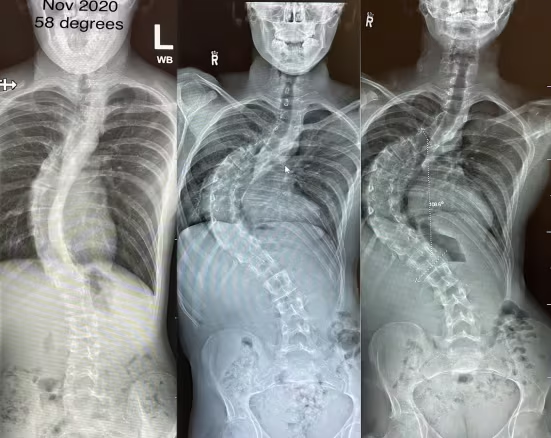

ما مدى خطورة اعوجاج العمود الفقري عند الأطفال؟ دليل مبسط للأهل لفهم الحالة وطرق العلاج يُعد اعوجاج العمود الفقري عند الأطفال، أو ما يُعرف طبيًا بالجنف، من الحالات التي قد تثير قلق الأهل عند

هل فات الأوان لارتداء حزام اعوجاج العمود الفقري؟ إليك السن الأمثل وفعالية الحزام يطرح الكثير من الآباء والمرضى سؤالًا مهمًا عند اكتشاف اعوجاج العمود الفقري: هل فات الأوان لارتداء الحزام؟وغالبًا ما يظهر هذا القلق